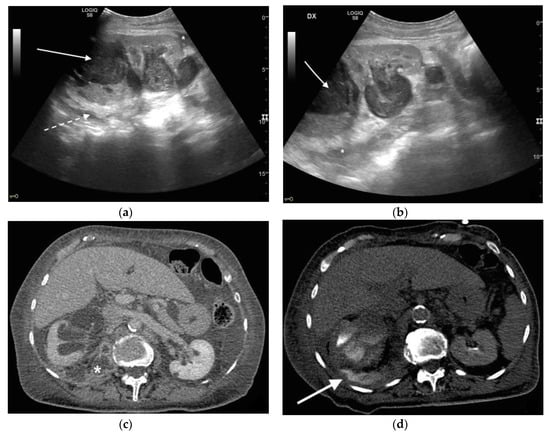

3. Ultrasound

4. CT